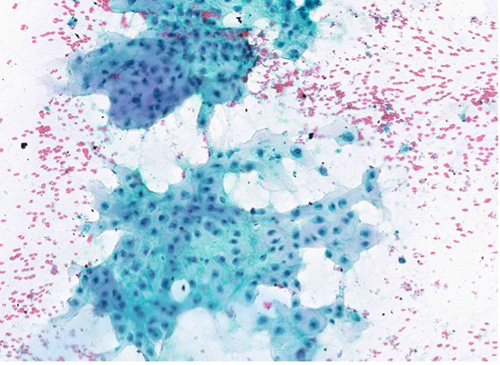

Cytology Microscopic Findings and Ancillary Studies

Examination of the cytologic smears revealed a hypercellular specimen composed of multiple clusters of atypical epithelioid cells with eccentric nuclei and cytoplasmic vacuoles, in a background of abundant extracellular chondro-myxoid matrix material (greenish blue appearance on Papanicolaou-stain slides).

Papanicolaou stain (100X)

Papanicolaou stain (400X)

The clinical history, radiologic findings along with the cytomorphologic features are highly suspicious for a malignant process. Our differential diagnoses primarily includes a chondrosarcoma arising from thyroid cartilage and to a lesser degree an anaplastic thyroid carcinoma with chondrosarcomatous differentiation. A more remote possibility would include a chordoma.

Immunohistochemical studies were performed on direct smears and were negative for keratins (AE1/AE3) and TTF-1 (Thyroid Transcription Factor-1). S100 (not verified) was positive in tumor cells.

In light of the morphologic and immunohistochemical findings, a diagnosis of chondrosarcoma was favored. A subsequent CT Neck and core biopsy were performed for definitive tissue diagnosis.